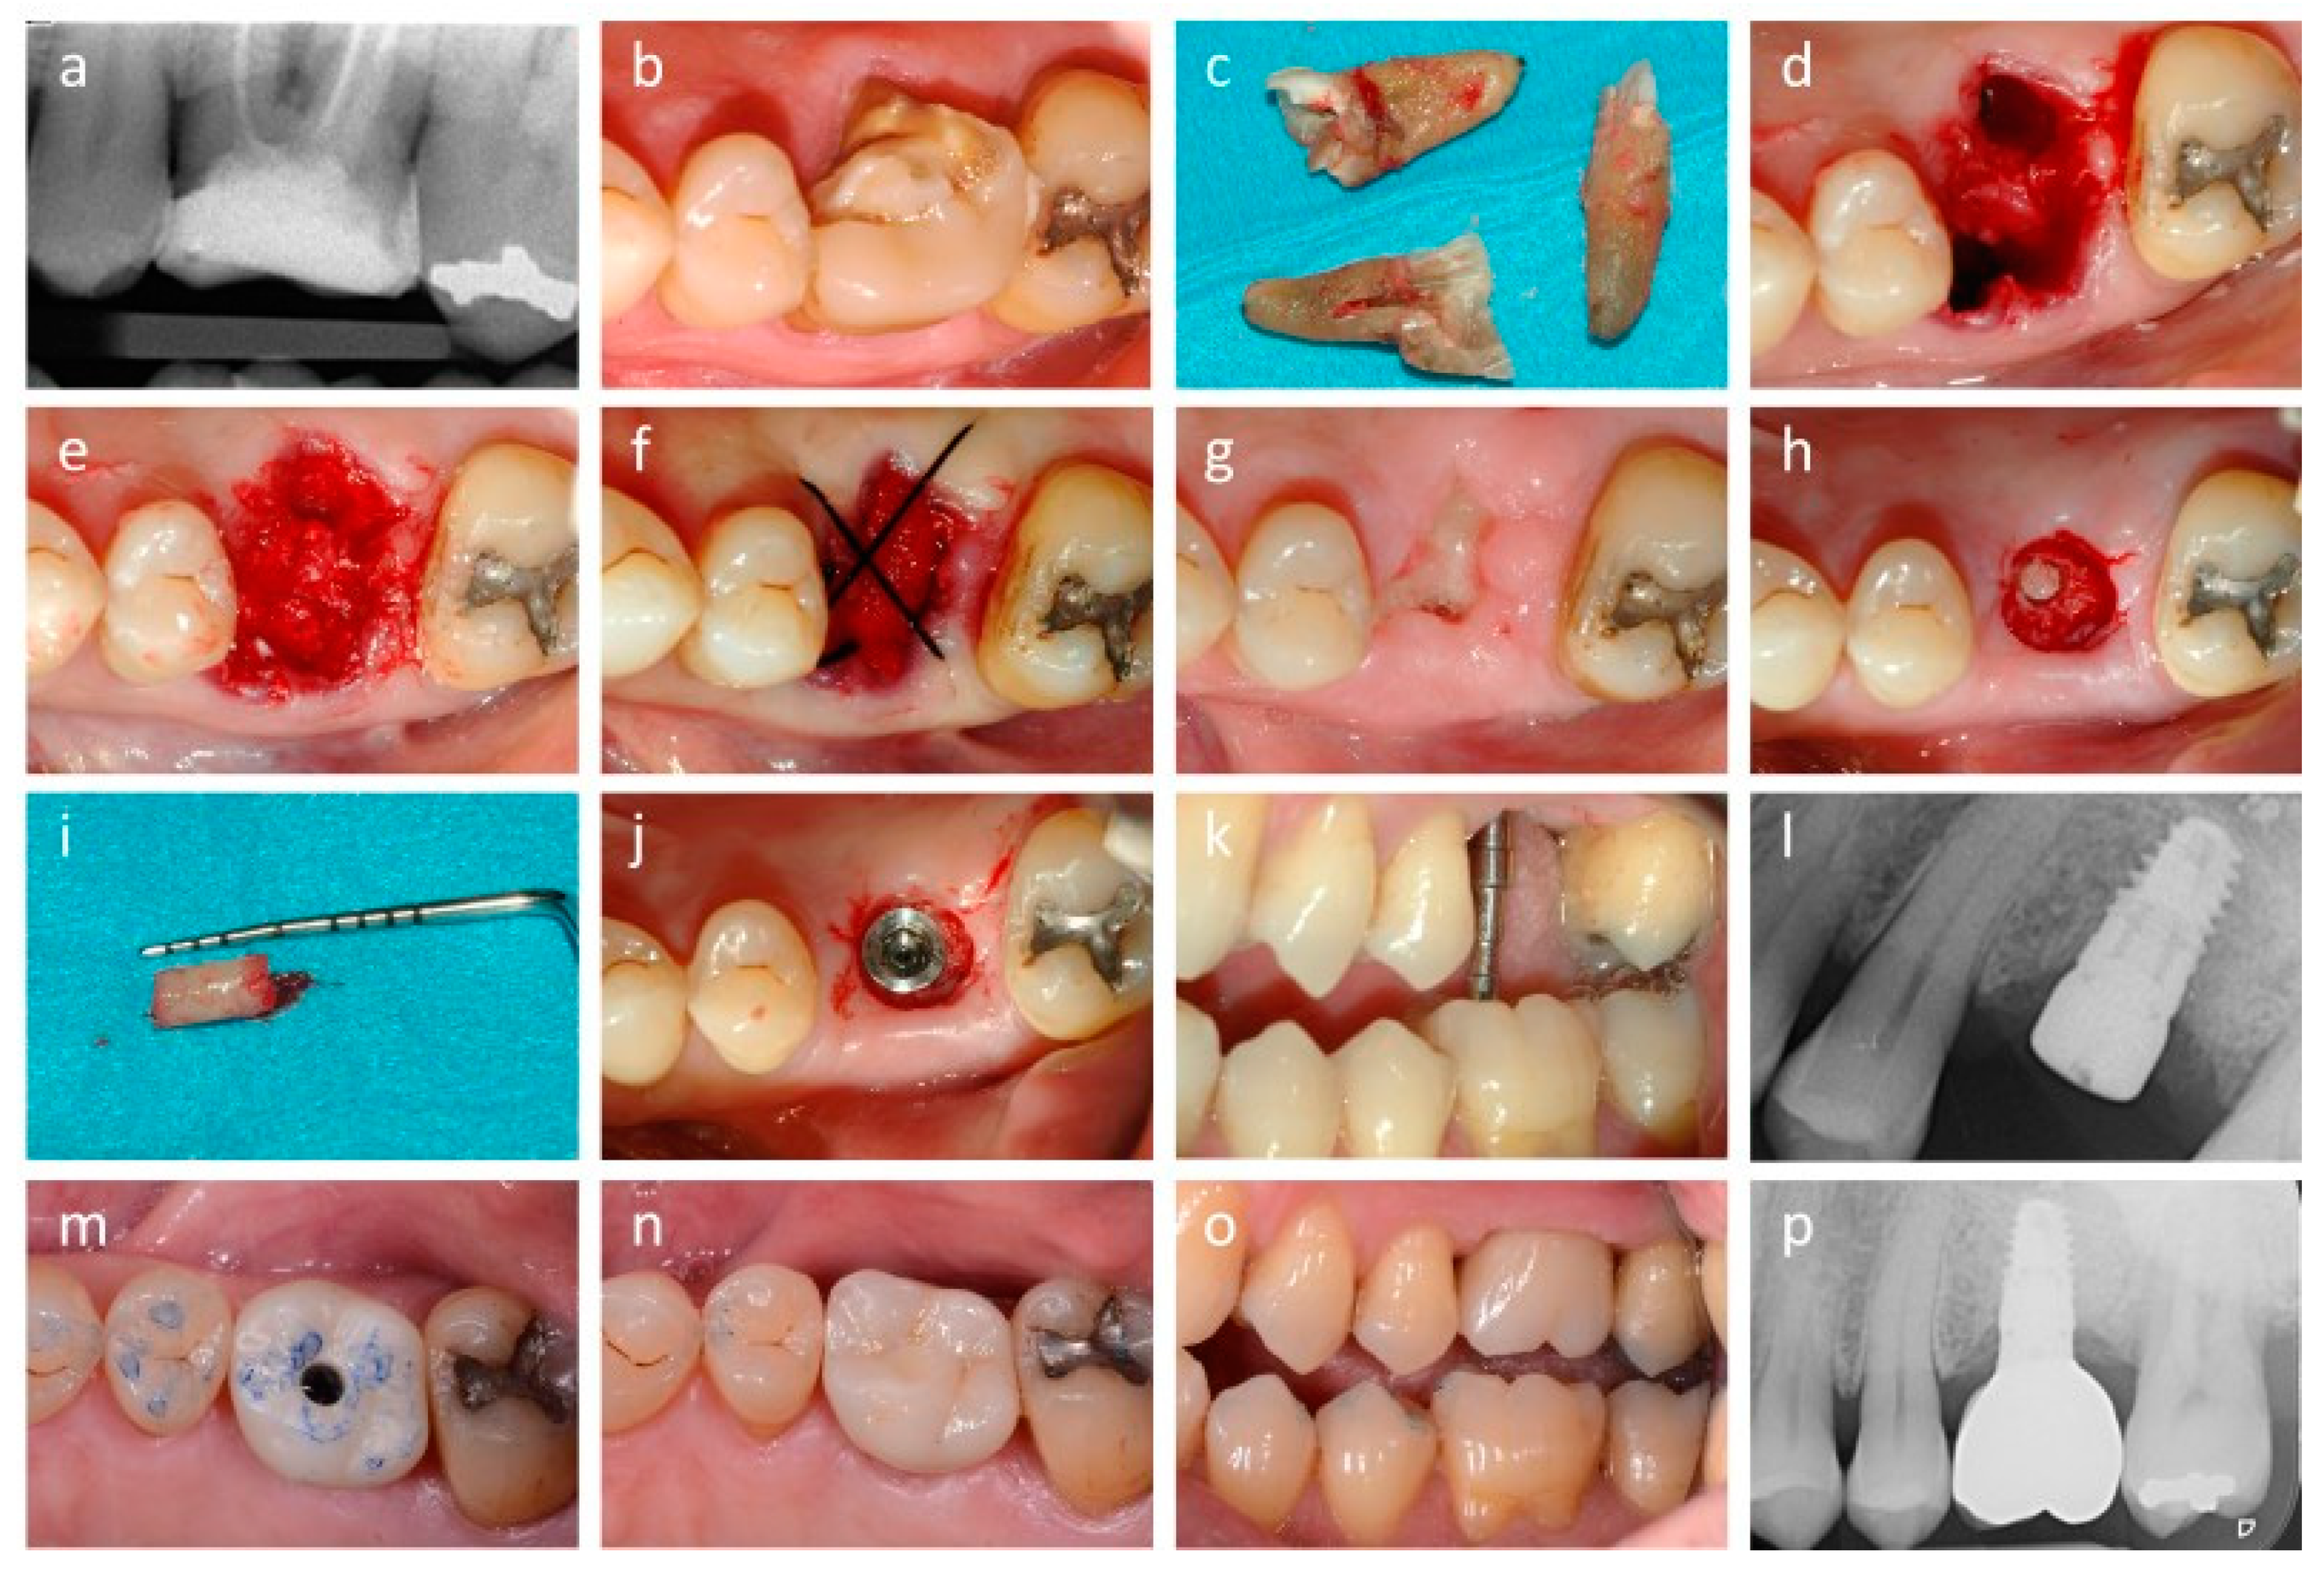

2.2. Extraction, Grafting and Implant Surgery

2.3. Histologic and Histomorphometric Analysis

2.4. Implant Success and Peri-Implant Marginal Bone Loss